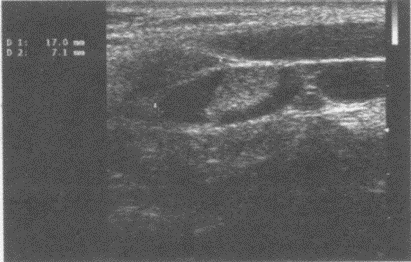

99、单项选择题

患者,男性,甲状腺一侧可触及包块,超声见边界清晰的低回声光团,包膜完整。如图所示,最可能的诊断为()。

A.甲状腺腺瘤并囊性变

B.甲状腺炎

C.结节性甲状腺肿

D.甲状腺癌

E.甲状腺囊肿

100、单项选择题

如图,正常甲状腺中部横切面的超声声像图,中央气管环状软骨前方组织为()。

A.甲状腺峡部